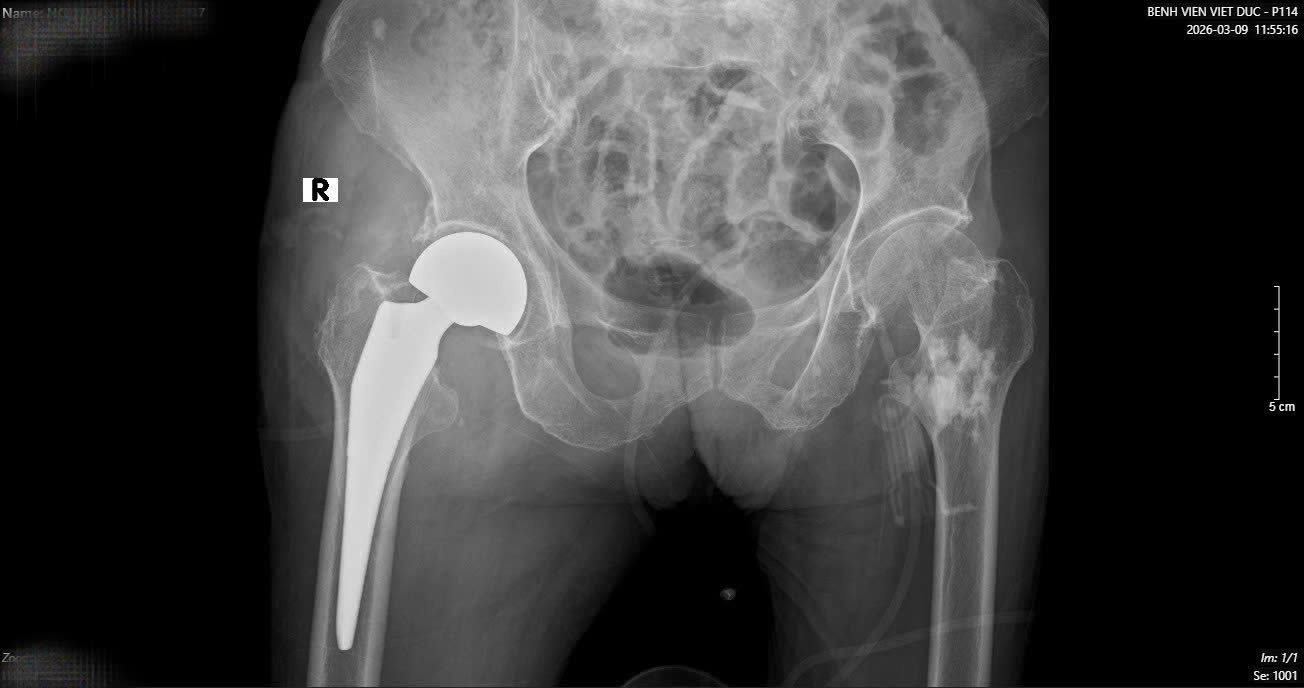

Hình ảnh phim X-quang cụ bà 89 tuổi nhập viện gãy cổ xương đùi phải và hình ảnh chụp CT ổ bụng và phát hiện khối u ruột non gây lồng ruột.

Sau một tuần, khi các chỉ số sức khỏe ổn định, cụ bà tiếp tục bước vào cuộc đại phẫu thứ hai. TS.BS Hoàng Ngọc Sơn đã trực tiếp phẫu thuật thay khớp háng cho cụ. Nhờ sự chuẩn bị kỹ lưỡng của đội ngũ y bác sĩ, ca mổ đã thành công tốt đẹp.

Chỉ sau một tuần thay khớp, cụ bà đã có thể tập đi và vận động gần như bình thường. Đây là kết quả rất khả quan đối với một bệnh nhân cao tuổi vừa trải qua hai cuộc đại phẫu liên tiếp trong vòng 16 ngày.